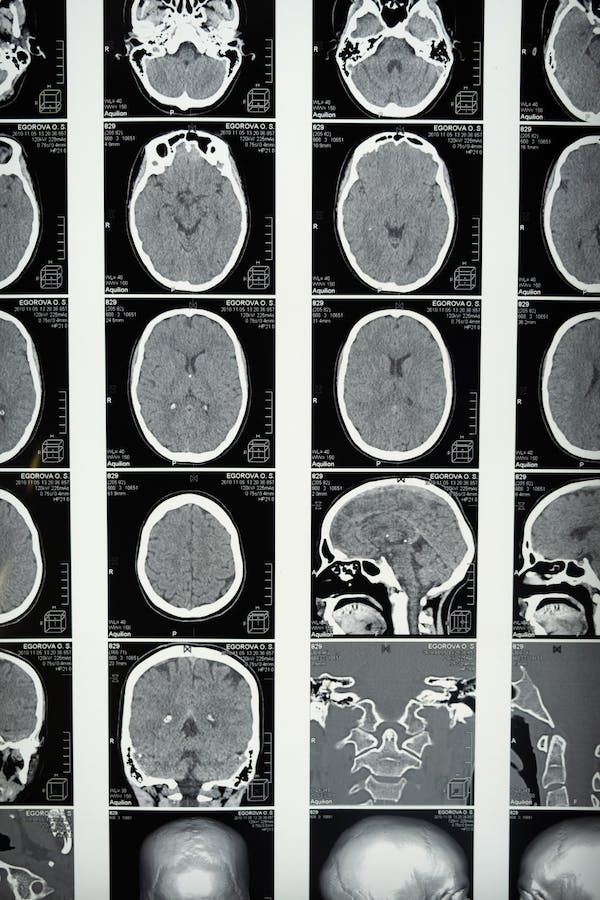

La afasia de Wernicke se produce, como no puede ser de otro modo, mediante la afectación del área de Wernicke. Esta zona se encuentra en la porción posterior del lóbulo temporal superior, en estrecha proximidad con el área auditiva primaria. Se extiende hacia la cisura de Silvio y está delimitada anteriormente por el área de Brodmann 22.

Específicamente, se subdivide en dos regiones conocidas como el área de asociación auditiva temporal superior y el área de asociación visual temporal inferior. Así, su principal función es la comprensión del lenguaje, ya sea a través de los estímulos auditivos o visuales que llegan a la persona.

Las causas de la afasia de Wernicke suelen estar asociadas con daños en el lóbulo temporal posterior y el lóbulo parietal superior, concretamente en la región perisilviana de la corteza cerebral. Estas lesiones pueden ser resultado de diversos factores, tales como (Zhang et al., 2006):

- Accidente cerebrovascular (ACV): La causa más común de la afasia de Wernicke es la interrupción del suministro sanguíneo al área de Wernicke debido a un ACV. Por ejemplo, un accidente cerebrovascular isquémico, que ocurre cuando un vaso sanguíneo se obstruye, o un accidente cerebrovascular hemorrágico, causado por la ruptura de un vaso sanguíneo, pueden dañar dicha zona y provocar la afasia.